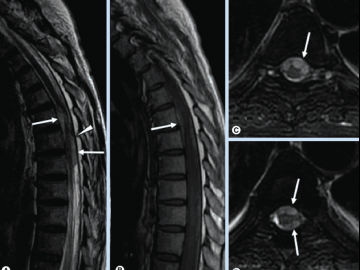

– Как выглядит грыжа позвоночника на снимке МРТ?

– Доктор видит выпячивание диска, может оценить размер и направление выпячивания, а также, что немаловажно, сужение просвета корешковых каналов, обуславливающее такую симптоматику, как боли и онемение в руках или ногах.

Особенности метода МРТ позволяют оценить не только снижение высоты межпозвонкового диска, но и уменьшение гидратации пульпозного ядра.

Грыжа позвоночника на МРТ

Рассматривая снимок, полученный с помощью МРТ, можно подробно рассмотреть межпозвонковую структуру. На нем видно, как пульпозное ядро выпячивается, а позвонки становятся намного ближе друг к другу. Грыжевое выбухание может быть направлено в разные стороны, создавать давление на нервные корешки близлежащих структур. С помощью томограмм легко определить вид грыжи. Она бывает локальная, а также секвестрированная. Последняя относится к тяжелой форме разрушения межпозвонкового диска, когда состав ядра диска выпадает и отходит от места грыжи.